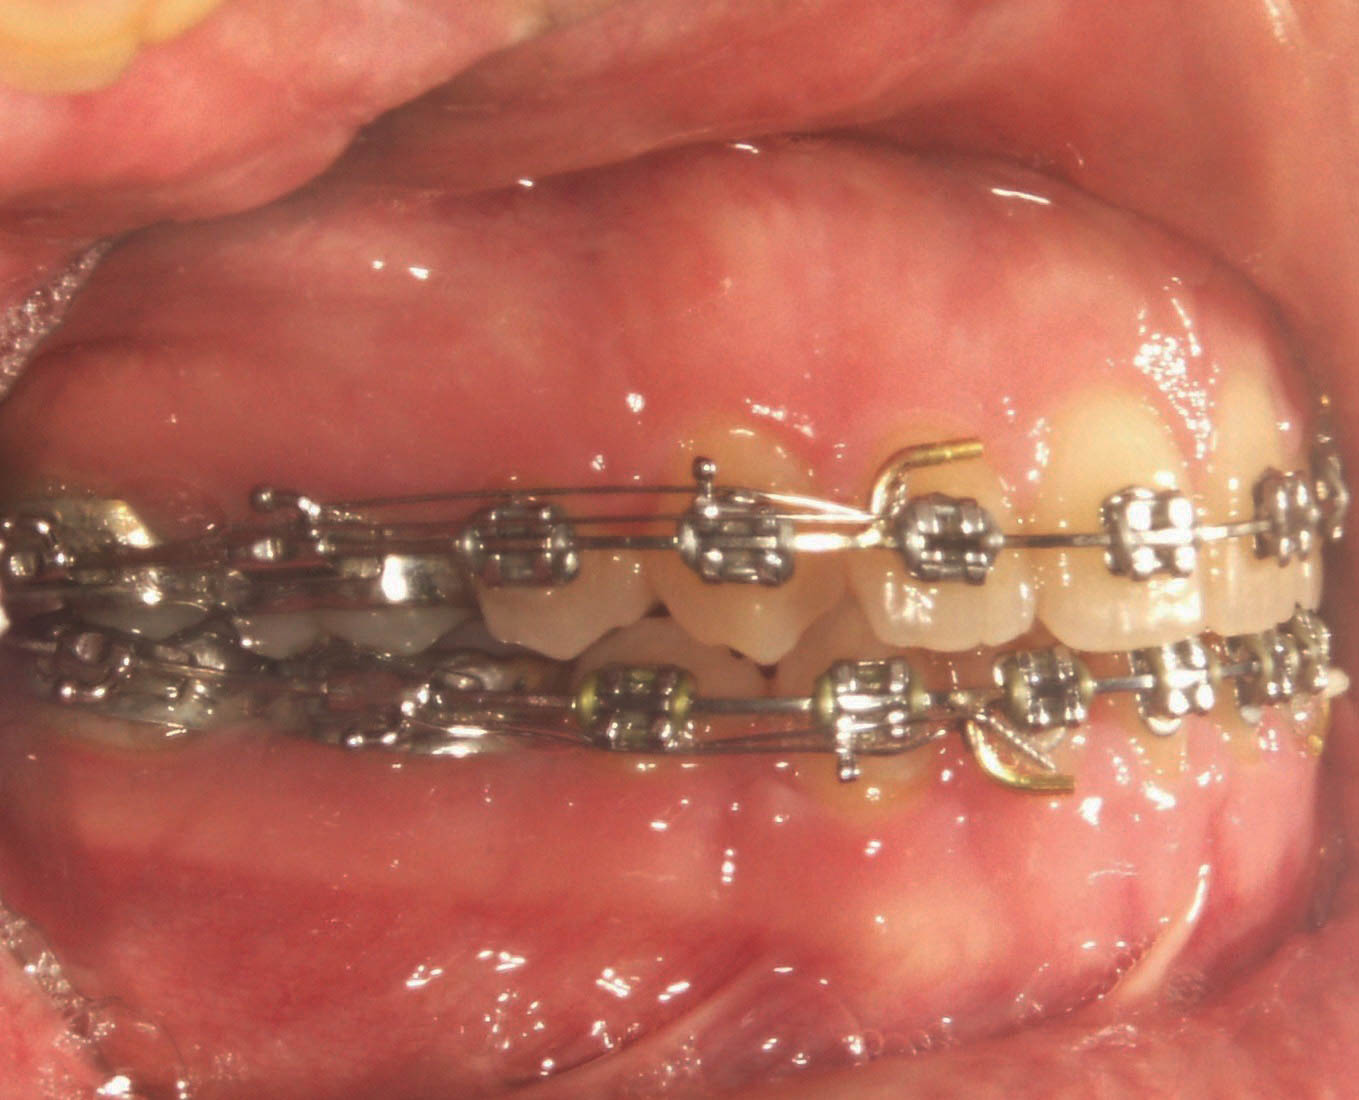

هر وقت فضای یک سمت بسته شد باید یک Passive Tieback بزنید تا مجدداً باز نشود (شکل 44-4).

شکل 44-4: زدنPassive Tieback بعد از بسته شدن فضا به مدت یک ماه تا مجدداً باز نشود.